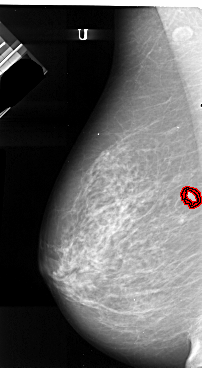

A_1065_1.RIGHT_CC

LEFT_MLO LINES 5506 PIXELS_PER_LINE 3016 BITS_PER_PIXEL 16 RESOLUTION 42 OVERLAY

FILE: A_1065_1.LEFT_MLO.OVERLAY

TOTAL_ABNORMALITIES 1

ABNORMALITY 1

LESION_TYPE MASS SHAPE IRREGULAR MARGINS SPICULATED

ASSESSMENT 5

SUBTLETY 4

PATHOLOGY MALIGNANT

TOTAL_OUTLINES 2

BOUNDARY

CORE